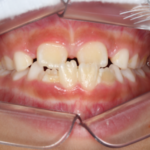

治療途中の矯正の症例

Before After 治療途中の小児矯正の症例です。あごの成長を利用しながら ...